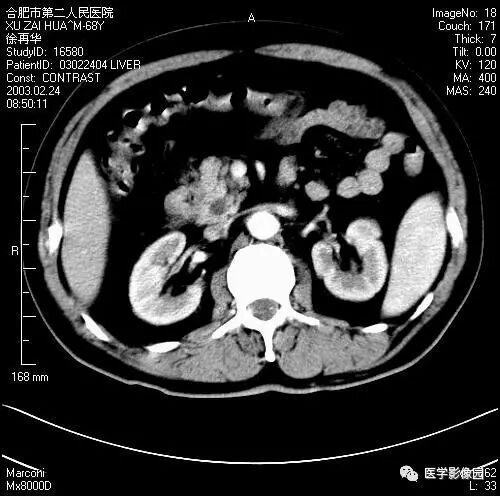

图6-4-14胰腺癌

A.CT平扫见胰体、尾部分叶状肿块,

其内见境界不清的低密度区;

B.增强扫描肿块内低密度更加清晰